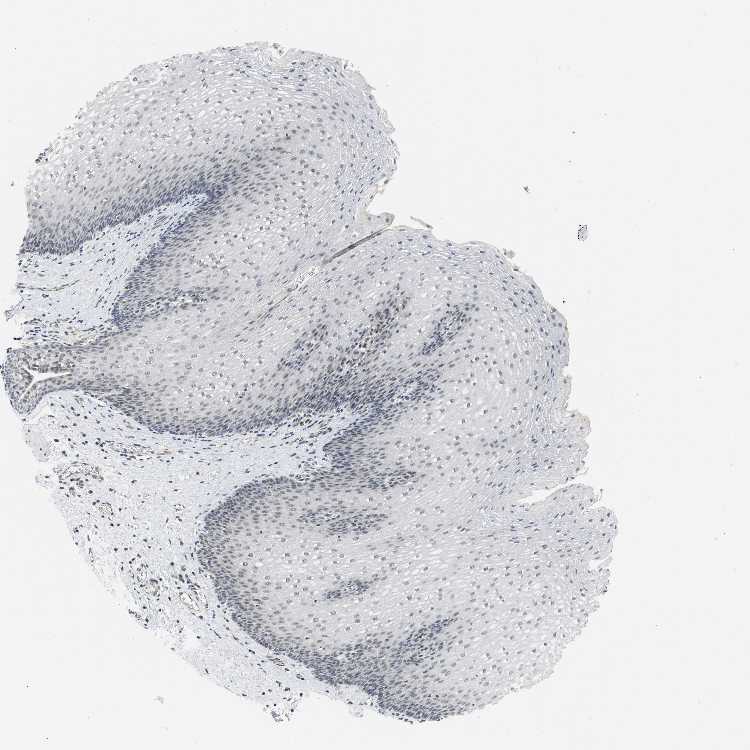

ESOPHAGUS - Antibody stainingi

Antibody staining in the annotated cell types in the current human tissue is reported as not detected, low, medium, or high, based on conventional immunohistochemistry profiling in selected tissues. This score is based on the combination of the staining intensity and fraction of stained cells.

Each image is clickable and will lead to virtual microscopy that enables deeper exploration of all samples and also displays staining intensity scores, fraction scores and subcellular localization as well as patient and tissue information for each sample.

Antibody HPA001757

Squamous epithelial cells Not detected